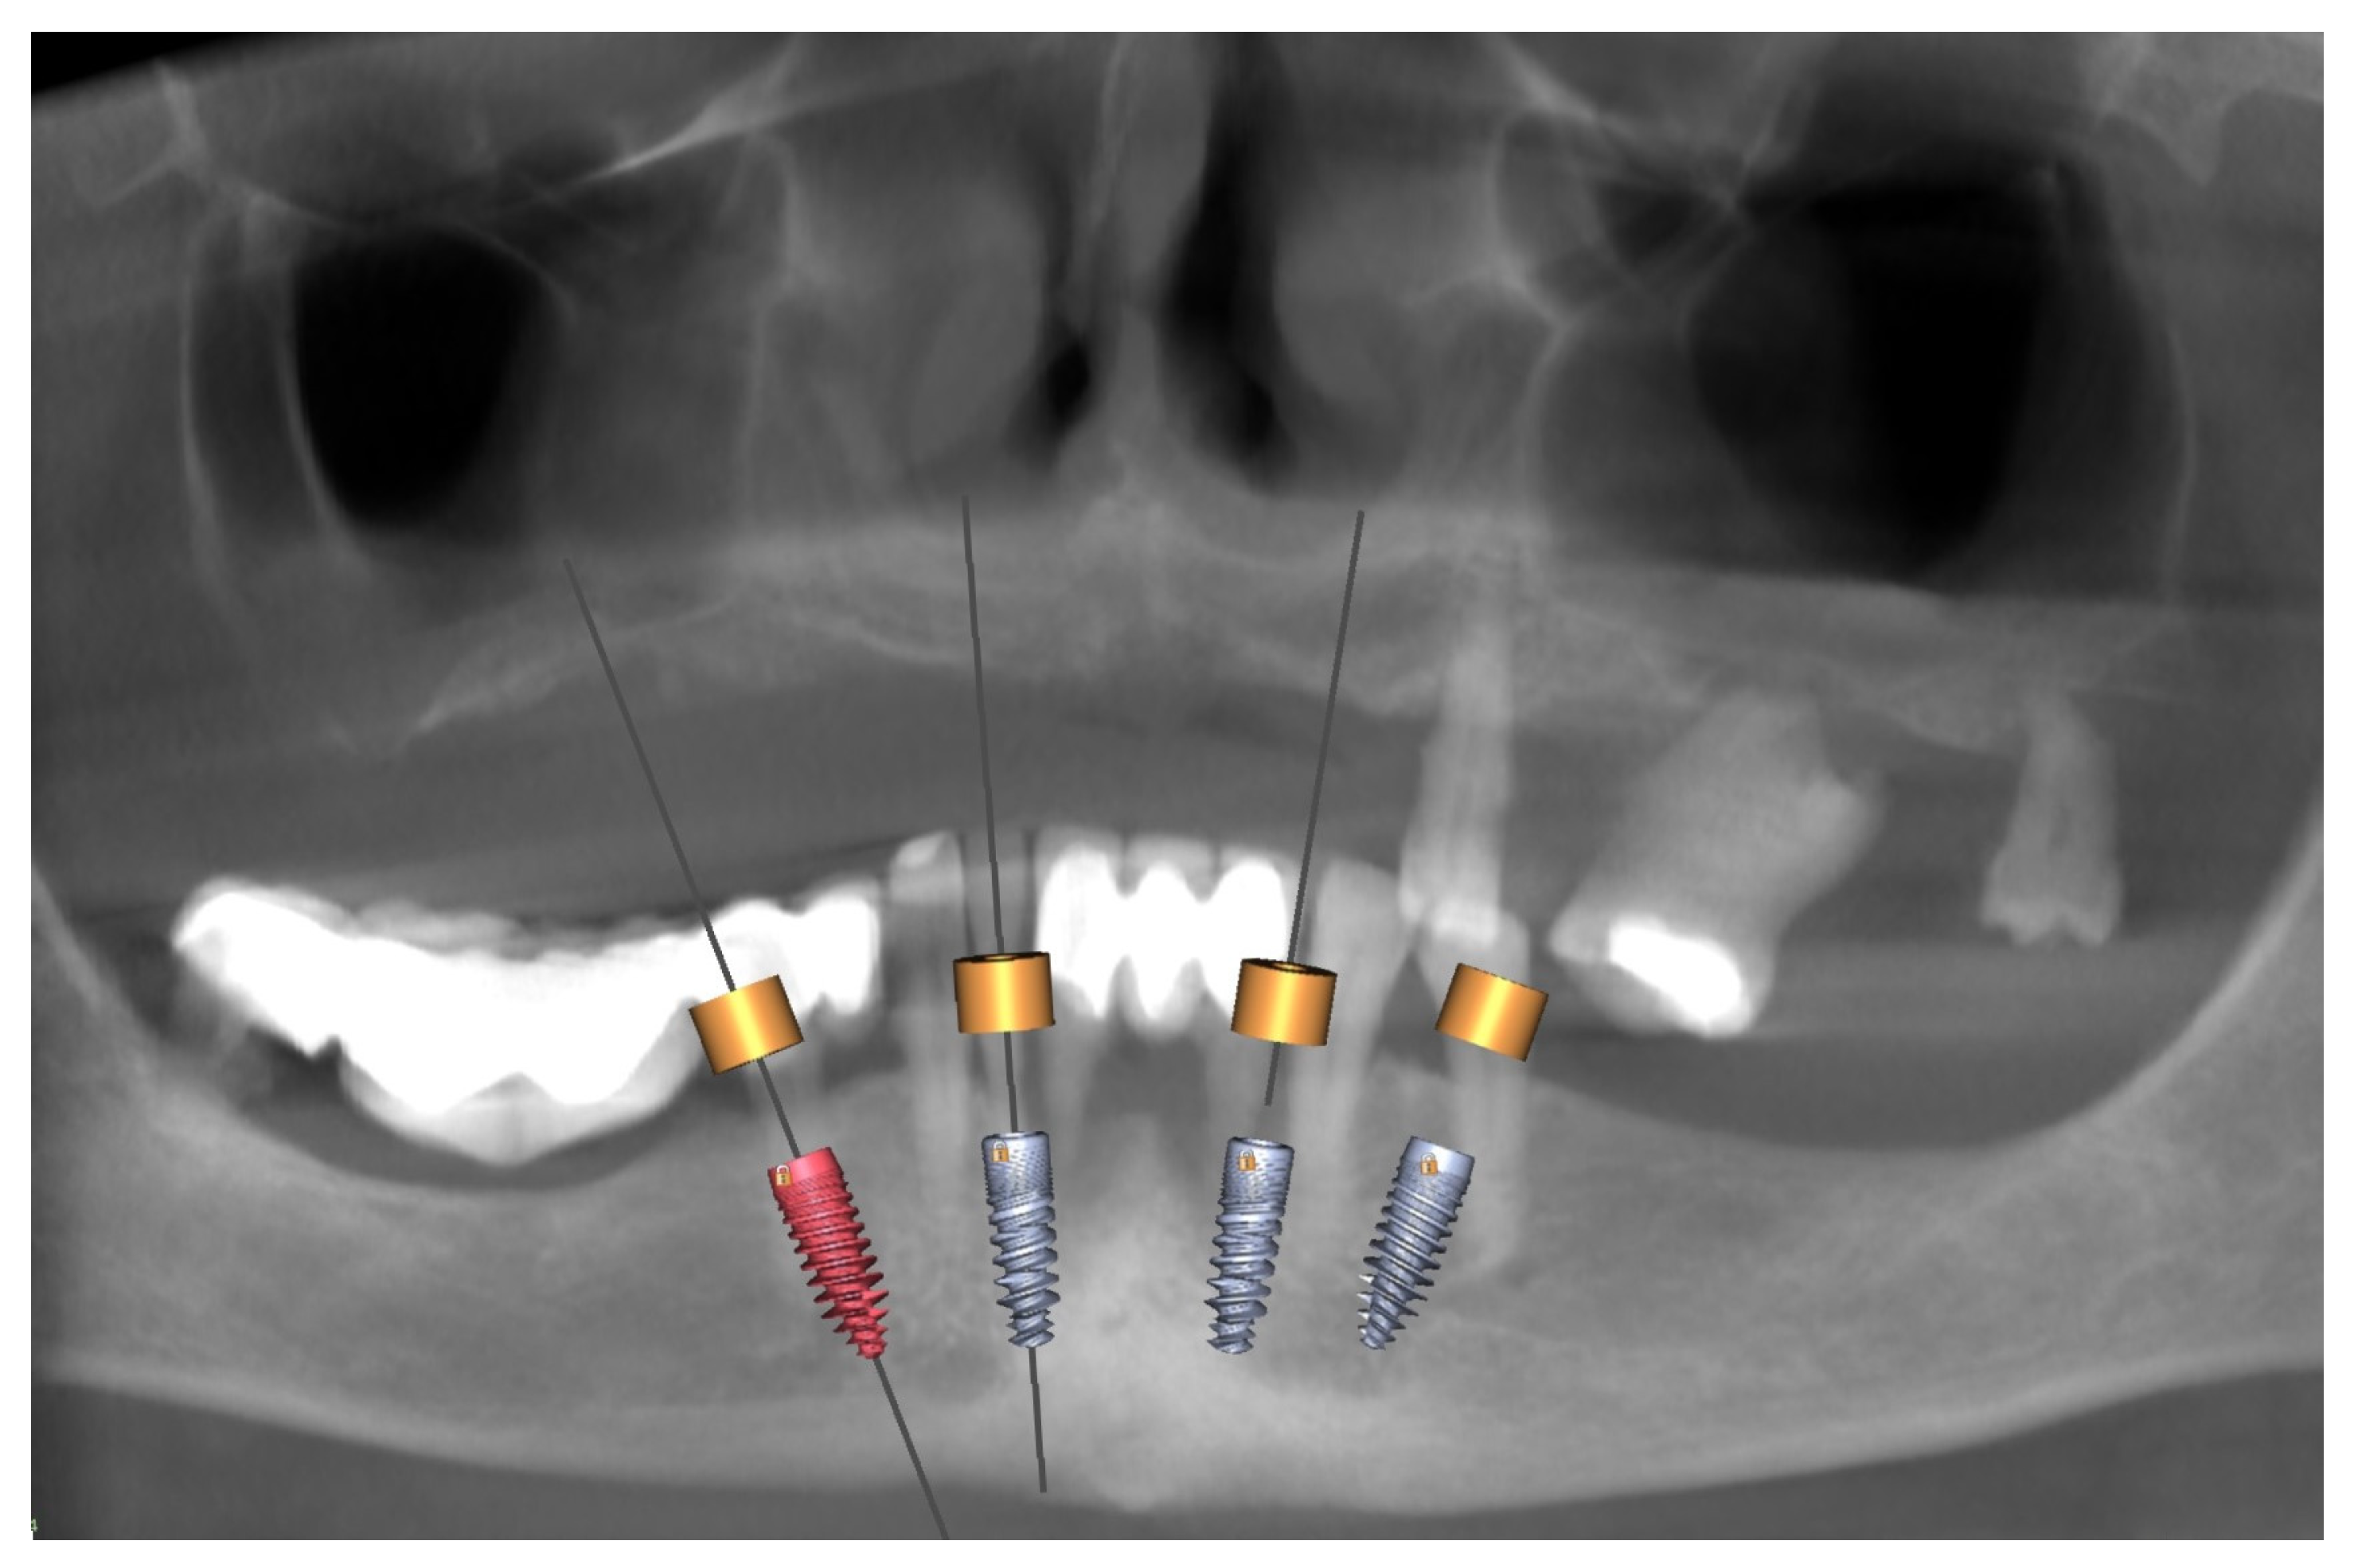

3.1. Planning and Preparation for the Treatment

3.2. Surgery in the Mandible and Immediate Loading—Stage I